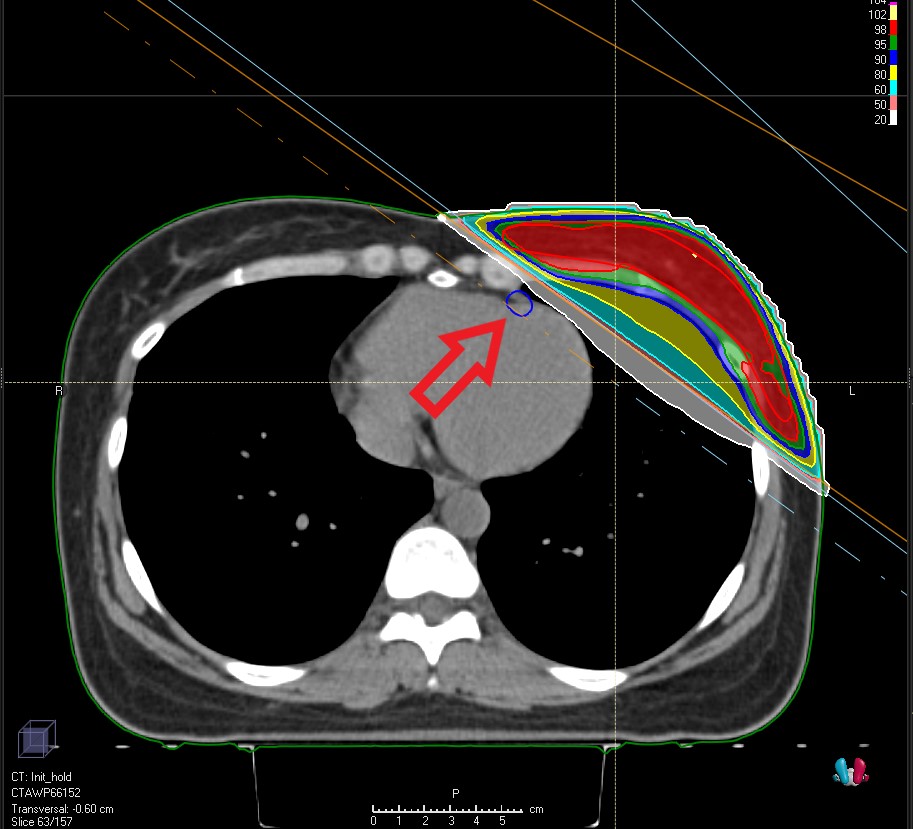

ÀÌ¿¡ ÇѸ²´ëÇб³µ¿Åº¼º½Éº´¿ø ¹æ»ç¼±Á¾¾çÇаú¿¡¼­´Â ¿ÞÂÊ À¯¹æ ¹æ»ç¼±Ä¡·á ½Ã ½ÉÀå¿¡ µé¾î°¡´Â ¹æ»ç¼±·®À» ÃÖ¼ÒÈ­Çϱâ À§ÇØ ºê·¹½ºÈ¦µù(Breath Holding) ¹æ»ç¼±Ä¡·á¸¦ ½ÃÇàÇϰí ÀÖ´Ù.

ÀÌ Ä¡·á¹ýÀº ¿ÞÂÊ À¯¹æ¿¡ ¹æ»ç¼±Ä¡·á¸¦ ¹Þ´Â ȯÀÚ¿¡°Ô ¼ûÀ» µéÀ̸¶½Å ä À̸¦ À¯ÁöÇϸ鼭 Ä¡·á¸¦ ¹Þ°Ô ÇÏ´Â °ÍÀÌ´Ù. ¼ûÀ» µéÀ̸¶½Ã¸é Æó°¡ ºÎÇ®°í Ⱦ°æ¸·ÀÌ ³»·Á°¡¸é¼­ ¹æ»ç¼± Á¶»çºÎÀ§¿Í ½ÉÀåÀÌ ¸Ö¾îÁö°Ô µÈ´Ù.

Á¤È®ÇÑ ¹æ»ç¼± Á¶»ç¸¦ À§ÇØ ºñÀüRT»çÀÇ ¹æ»ç¼±Ä¡·á º¸Á¶±â±âÀÎ ¡®Align RT¡¯¸¦ Ȱ¿ëÇÑ Ç¥¸é À¯µµ ¹æ»ç¼±Ä¡·á ±â¹ýÀ» »ç¿ëÇϰí ÀÖ´Ù. »çÀü ¹æ»ç¼±¸ðÀÇÄ¡·á ½Ã ¼ûÀ» µéÀ̸¶½Ã°í ÂüÀº »óÅ·ΠCT¸¦ ÃÔ¿µÇÑ µÚ ¹æ»ç¼±Ä¡·á¸¦ ¼³°èÇÑ´Ù. ÀÌÈÄ Ä¡·á½Ç¿¡¼­ Align RT·Î ȯÀÚÀÇ Ã¼Ç¥¸éÀÇ ¿òÁ÷ÀÓÀ» ½Ç½Ã°£À¸·Î ÆÄ¾ÇÇÏ¸ç ¹æ»ç¼±Ä¡·á¸¦ ÇÏ´Â °ÍÀÌ´Ù. »çÀü CTÃÔ¿µ ½Ã ȯÀÚÀÇ Ã¼Ç¥¸é°ú ºñ±³ÇØ ÀÚ¼¼ ¿ÀÂ÷°¡ Å« °æ¿ì ÀÚµ¿À¸·Î Ä¡·á°¡ ÁߴܵǸç, ȯÀÚÀÇ ÀÚ¼¼ ¿ÀÂ÷´Â 0.1mm ´ÜÀ§±îÁö È®ÀÎÀÌ °¡´ÉÇÏ´Ù. ÀÌ·¯ÇÑ Ç¥¸é À¯µµ ¹æ»ç¼±Ä¡·á ±â¹ýÀ¸·Î ȯÀÚ°¡ ¼ûÀ» Âü°í À¯ÁöÇÒ ¶§ÀÇ Á¤È®ÇÑ À§Ä¡¿Í °¢µµ¸¦ °è»êÇÑ µÚ ½ÉÀåÀ» ÇÇÇØ ¹æ»ç¼±À» Á¶»çÇÒ ¼ö ÀÖ´Ù.